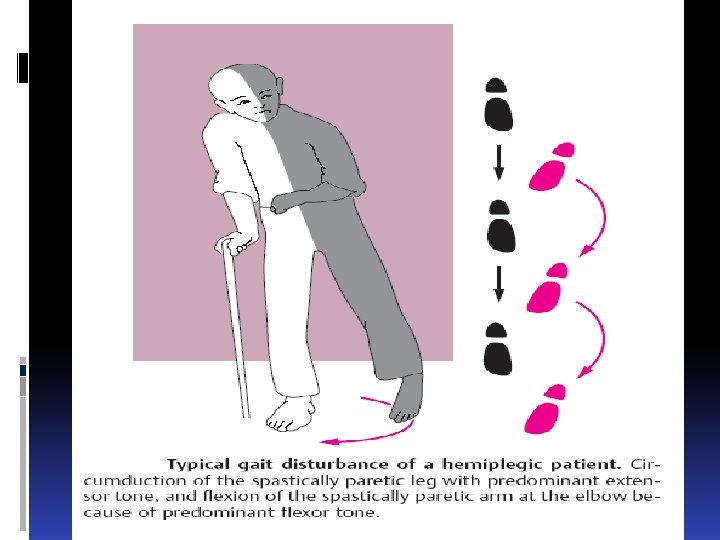

В бассейне А. cerebri media Астереогнозия Аутотопагнозия Слуховая агнозия Апраксия Агнозия Сенсомоторная афазия

В бассейне А. cerebri media Астереогнозия Аутотопагнозия Слуховая агнозия Апраксия Агнозия Сенсомоторная афазия